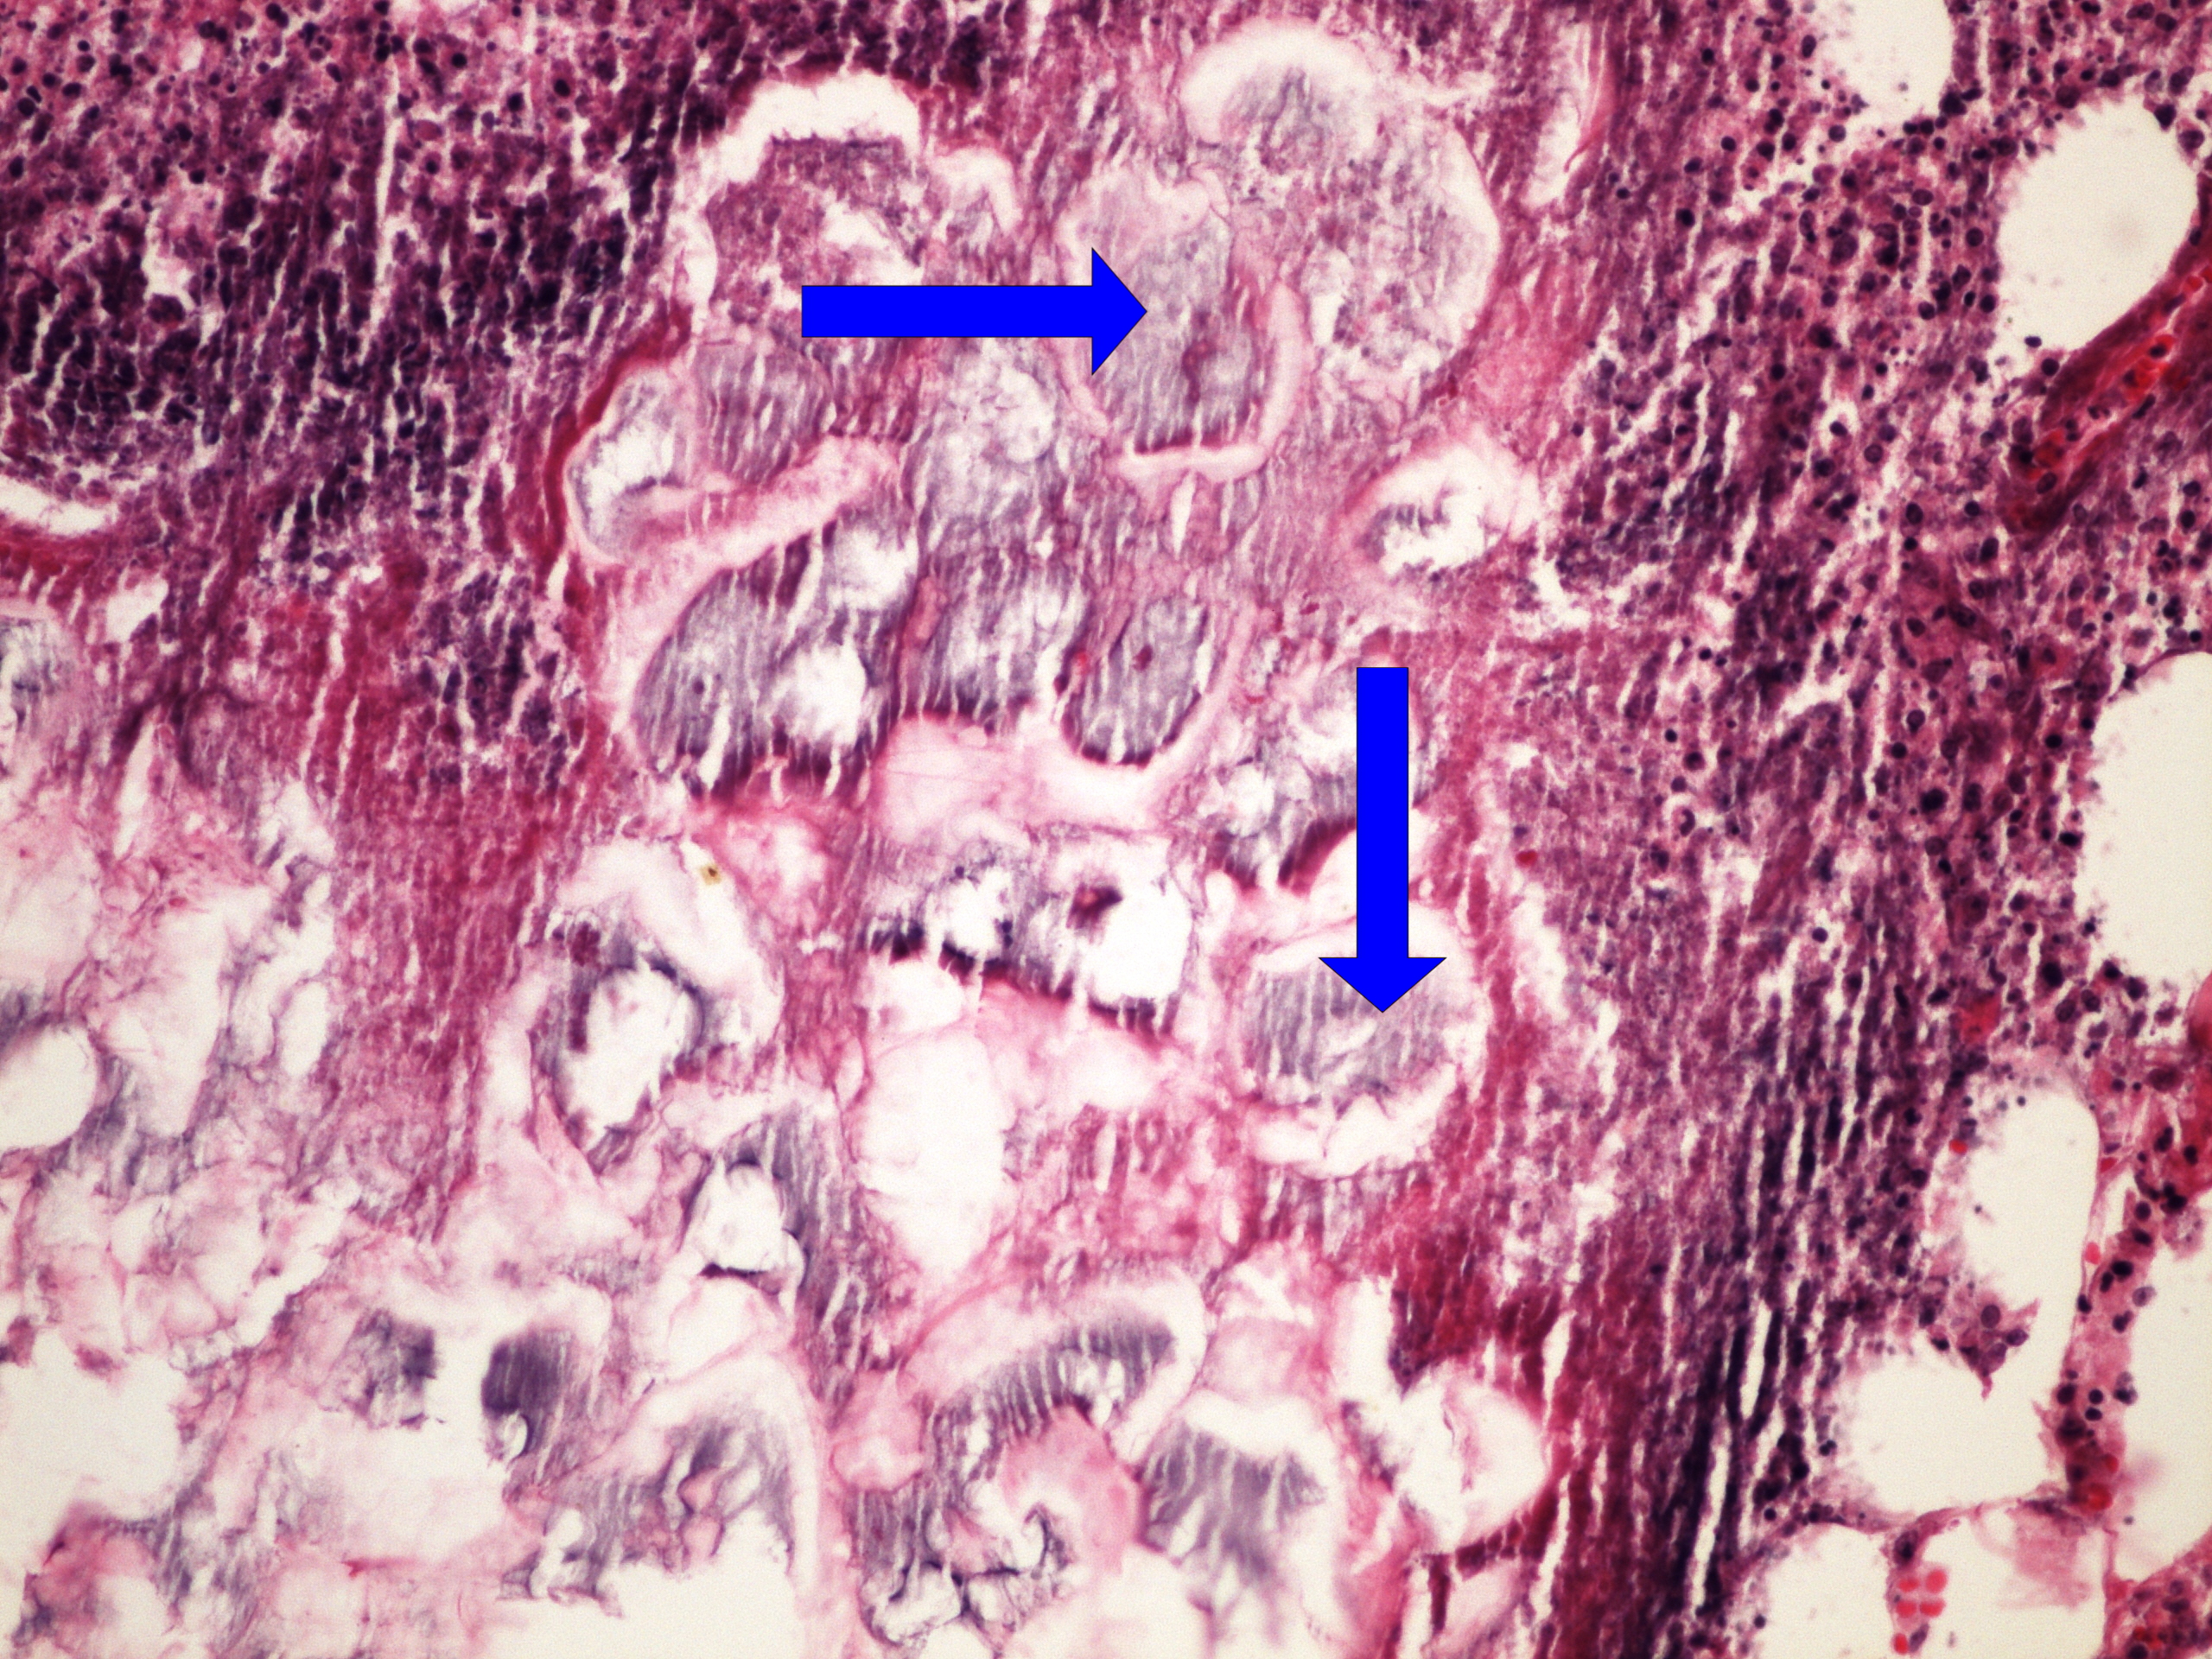

Preparát č.3 a č.4 - hepatitis (orcein)

Struktury

- pozitivní barvení na orcein u chronické hepatitidy B